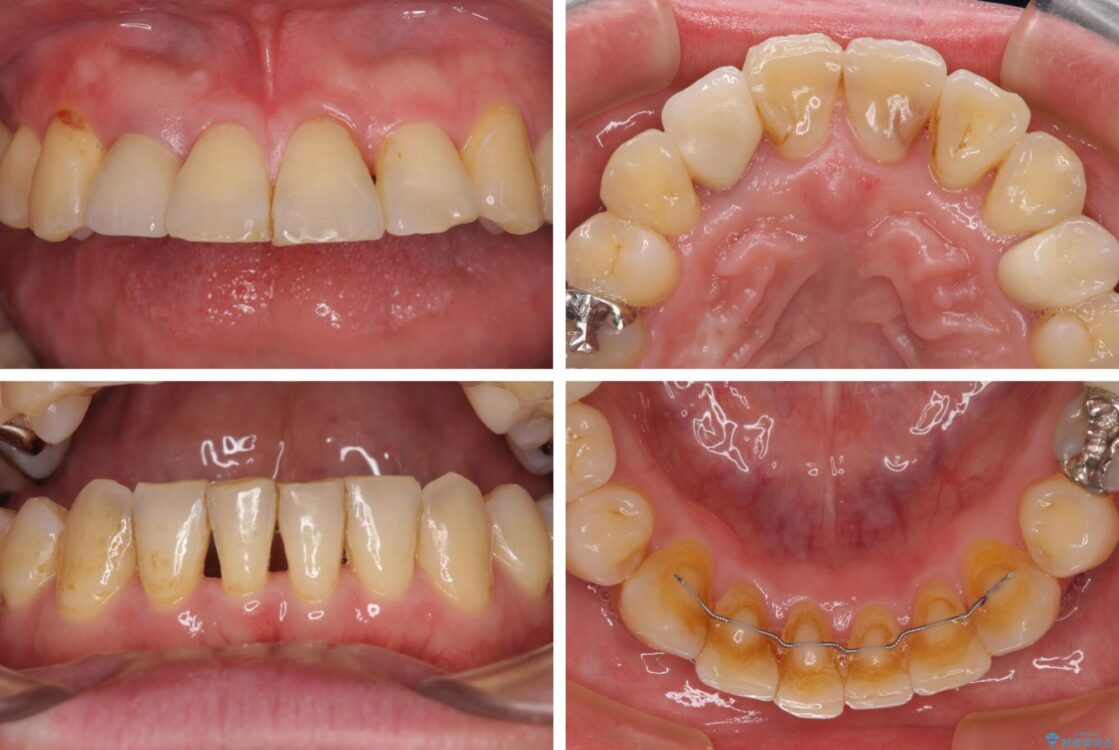

矯正治療でインプラント埋入を行い、矯正治療後に気になる前歯と合わせてオールセラミッククラウンによる補綴治療を行うこととしました。

治療後について

骨造成や歯肉移植など、治癒期間の長い処置を必要としたため治療期間は長くなりましたが、安定した咬み合わせと整った歯列となり、患者様には大変満足していただきました。

治療後